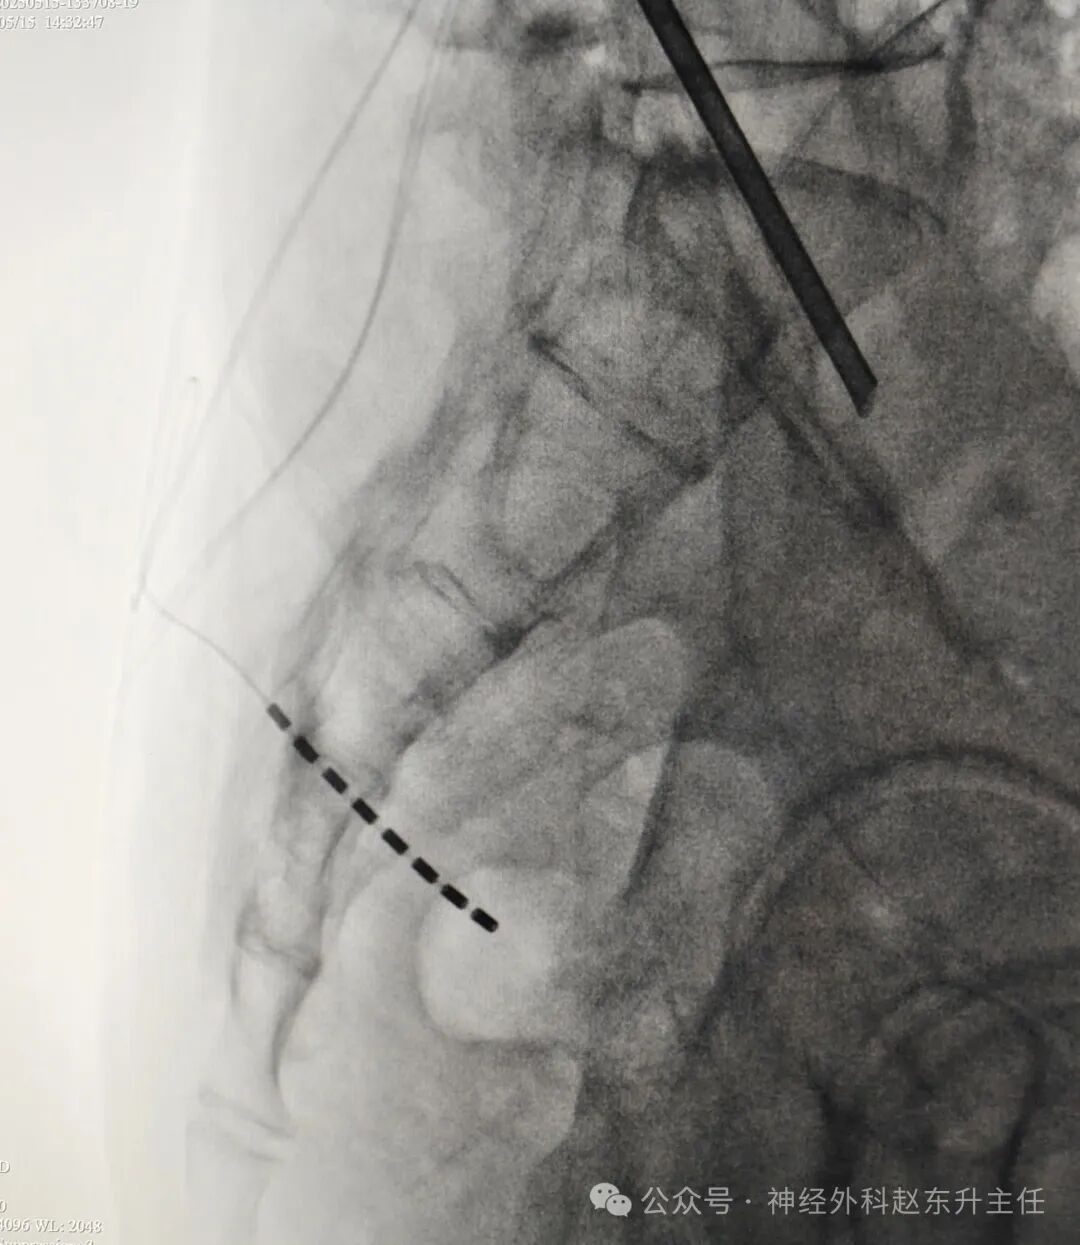

脊髓电刺激外科电极位置

IMG_20250515_151024.jpg

骶神经电极位置